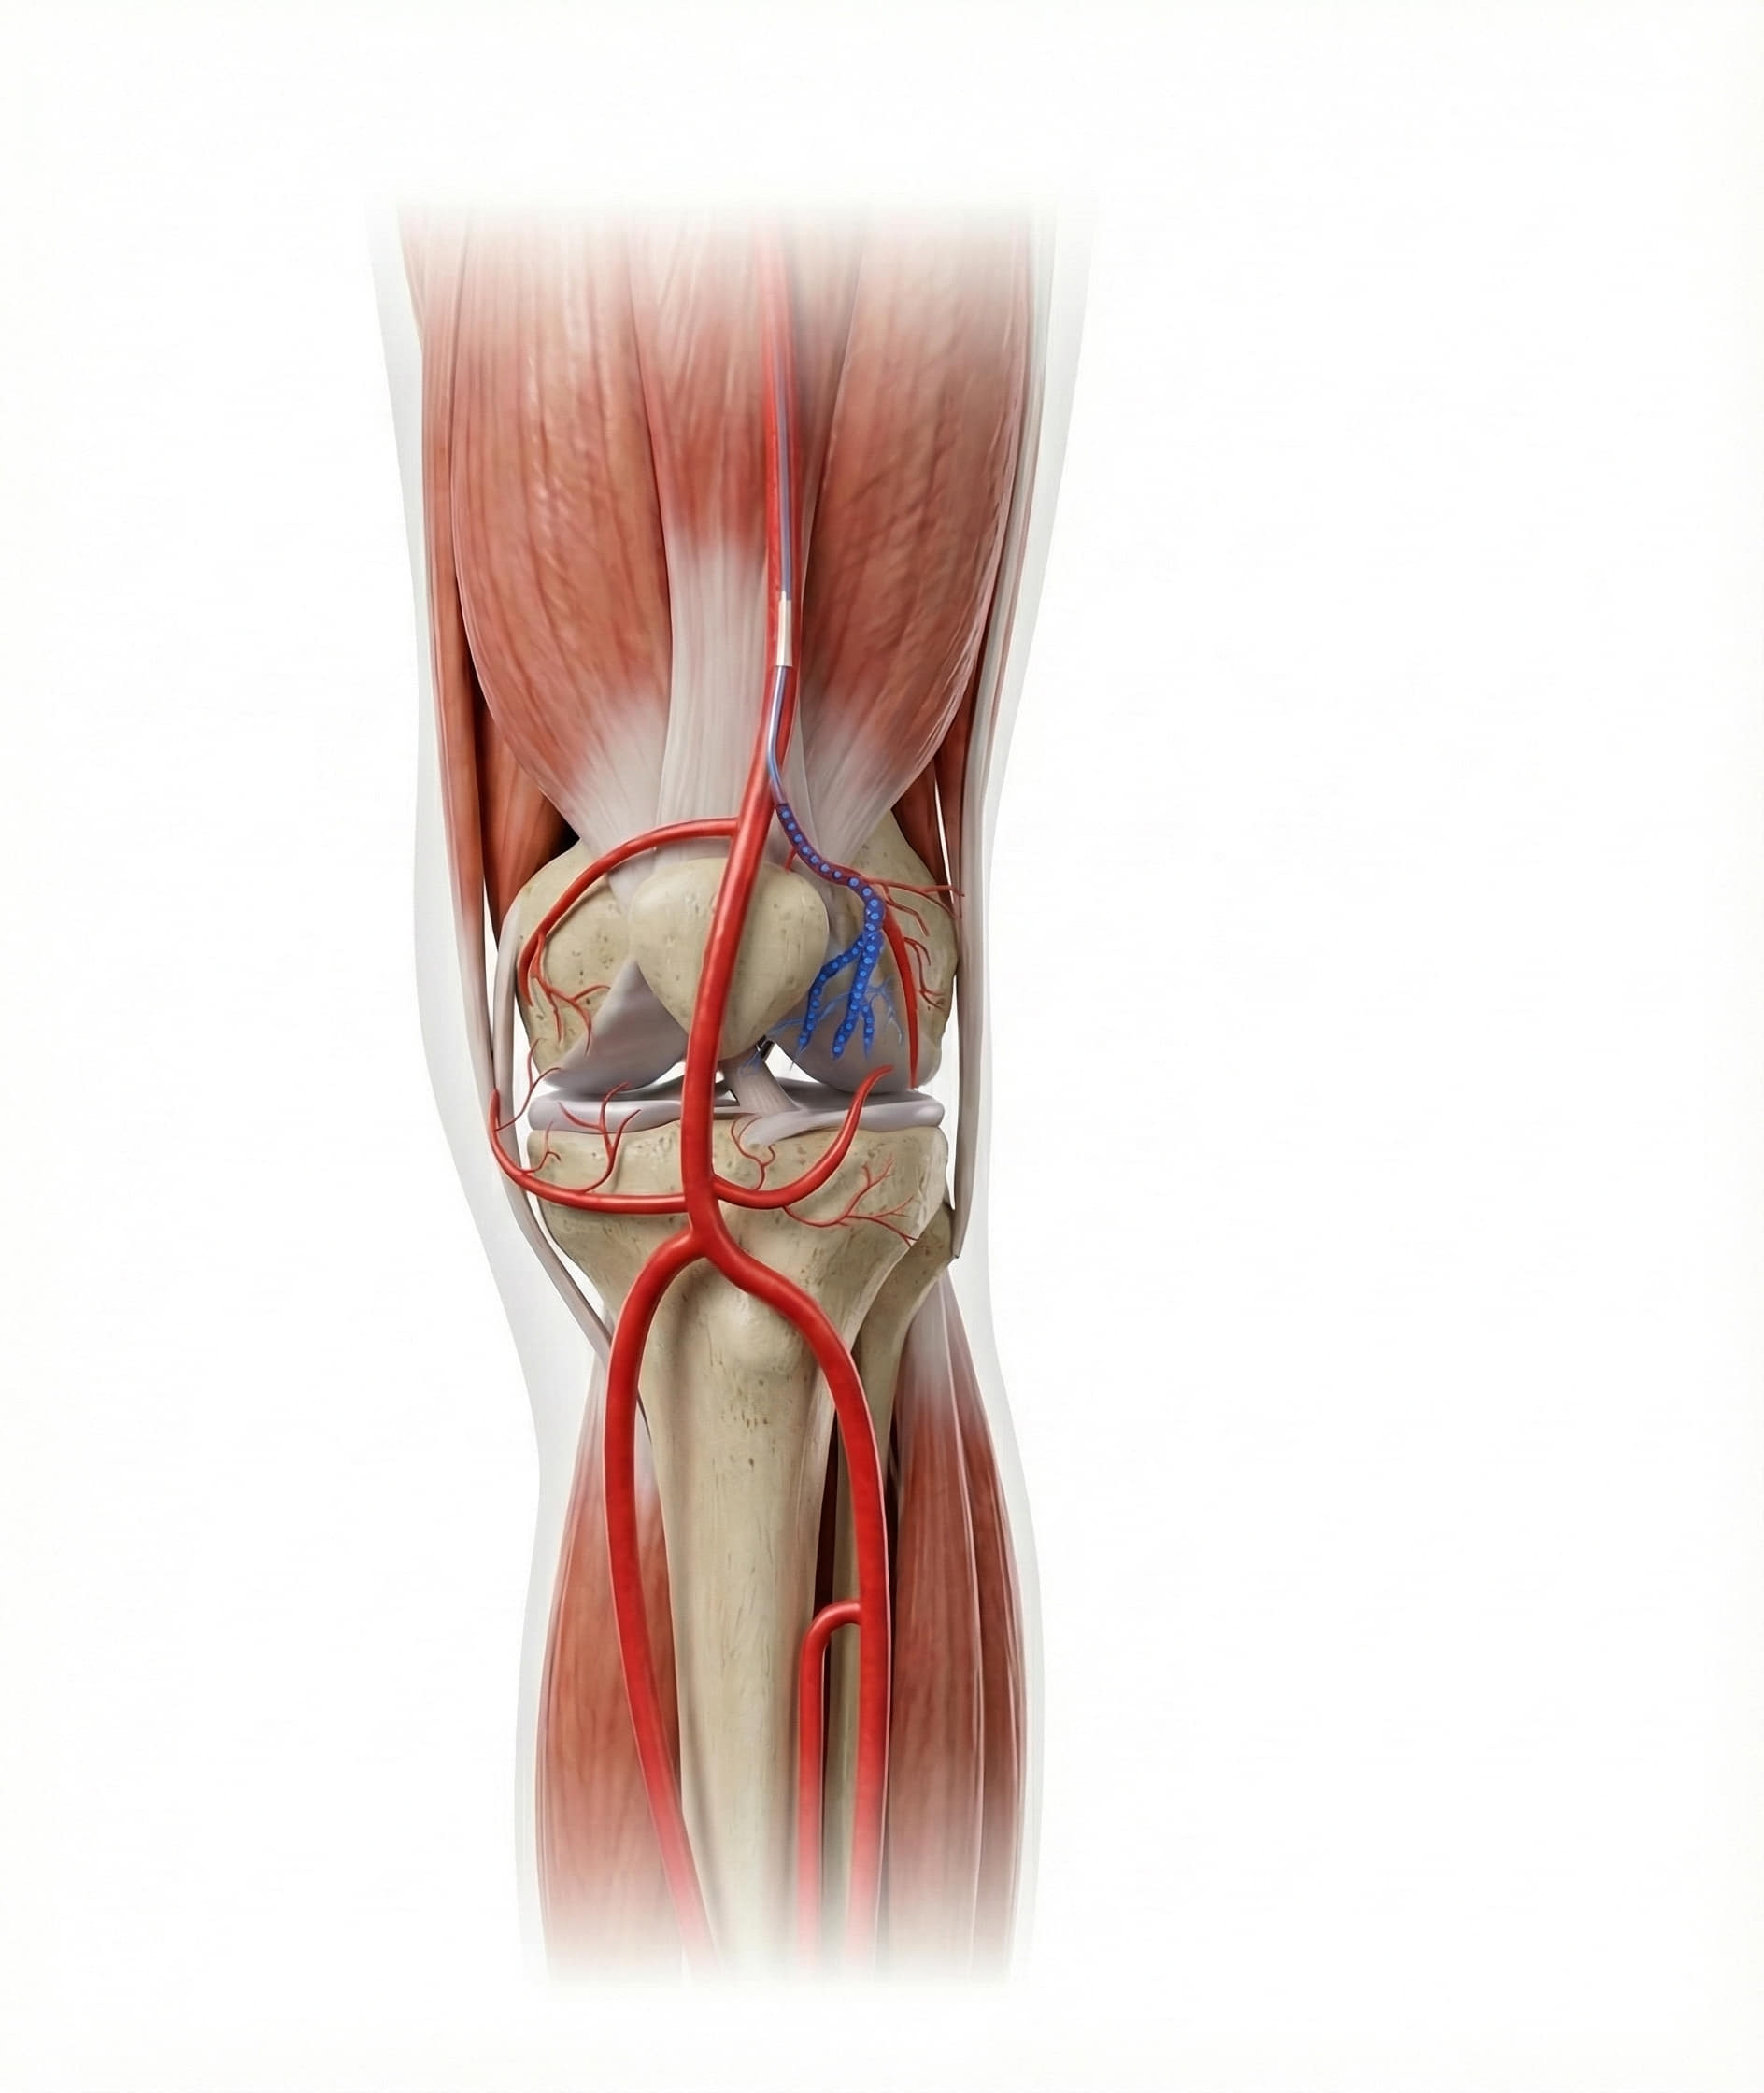

GAE is a novel, image-guided treatment developed to relieve chronic knee pain by blocking abnormal blood vessels in the joint. The procedure involves injecting tiny embolic agents—such as particles or coils—into specific genicular arteries, thereby reducing excess blood flow that fuels inflammation and pain.

In osteoarthritic joints, abnormal neovascularization—the formation of new, fragile blood vessels—plays a key role in inflammation and pain. GAE targets these vessels with precision:

- Step 1: Under angiographic guidance, the interventional radiologist maps the network of genicular arteries that supply the inflamed joint.

- Step 2: Embolic materials are introduced to selectively block these vessels.

- Step 3: Blood flow to the painful areas is reduced, leading to less inflammation and pain.

Why Anatomy Matters

Success depends heavily on the operator’s detailed knowledge of genicular artery anatomy, including its variations. Accurate targeting helps maximize efficacy and minimize risks like non-target embolization.